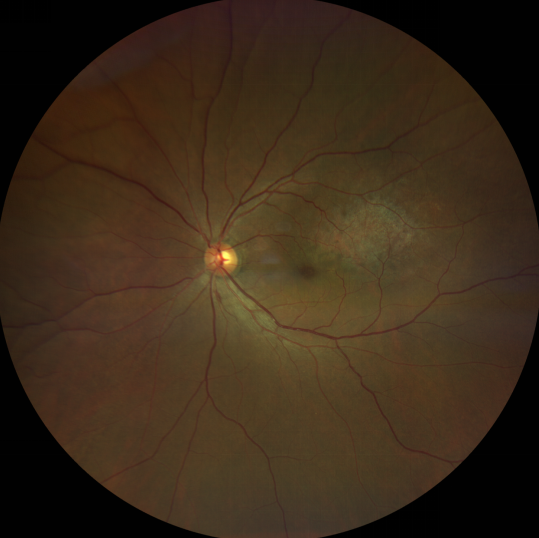

脈絡(luò)膜黑色素瘤是成年人常見(jiàn)的眼內(nèi)惡性腫瘤,其患病率在我國(guó)居眼內(nèi)惡性腫瘤的第二位,僅次于視網(wǎng)膜母細(xì)胞瘤。其惡性程度高,不僅可致患者喪失視力,而且嚴(yán)重威脅患者生命,即使在沒(méi)有明確轉(zhuǎn)移前摘除患眼眼球,其5年死亡率也有17%-53%。

脈絡(luò)膜黑色素瘤是葡萄膜惡性腫瘤中較多的一種。葡萄膜腫瘤主要發(fā)生于脈絡(luò)膜、睫狀體和虹膜。其中,脈絡(luò)膜腫瘤占80%,睫狀體腫瘤占12%,虹膜腫瘤占8%。惡性程度高的腫瘤主要發(fā)生于脈絡(luò)膜。發(fā)生于睫狀體的腫瘤惡性程度偏低,發(fā)生于虹膜的腫瘤多數(shù)為良性。脈絡(luò)膜黑色素瘤的特點(diǎn)是惡性程度高、易侵襲轉(zhuǎn)移、預(yù)后極差,嚴(yán)重威脅患者的視力和生命。其發(fā)病率有種族差異性,以高加索及白種人居多,黑人發(fā)病率低,亞洲人居于中間。

脈絡(luò)膜黑色素瘤患者在發(fā)病早期無(wú)眼痛等癥狀,當(dāng)腫瘤較小時(shí)較難發(fā)現(xiàn),隨著病程進(jìn)展,腫瘤增大,發(fā)生滲出性視網(wǎng)膜脫離或累及黃斑,視力下降才就診。

脈絡(luò)膜黑色素瘤惡性程度高,50%的患者會(huì)發(fā)生轉(zhuǎn)移,轉(zhuǎn)移到肝、肺等遠(yuǎn)處臟器,常見(jiàn)的轉(zhuǎn)移方式是經(jīng)鞏膜導(dǎo)管擴(kuò)散,經(jīng)視神經(jīng)蔓延者罕見(jiàn)。一旦發(fā)生轉(zhuǎn)移,1年生存率只有10%,即絕大多數(shù)病人在半年至1年間會(huì)失去生命。因此,早期診斷和選擇合適的治療方式對(duì)有效提高局部腫瘤的控制率、降低腫瘤的遠(yuǎn)處轉(zhuǎn)移率、延長(zhǎng)患者的生存率具有重要意義。